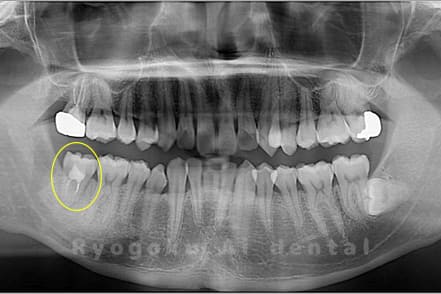

他院で根尖病変が大きく、抜歯と判断され、インプラント手術を提案された患者様です。親知らずが残存していたため、自家歯牙移植手術を行いました。

<リスク・副作用>

治療後、痛みや違和感、出血、腫れなどが出る事があります。喫煙者、糖尿病などの方の場合、歯が生着しない場合があります。